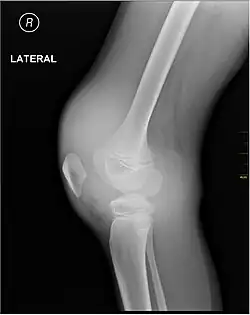

X-ray of Hemarthrosis -

X-ray of Hemarthrosis